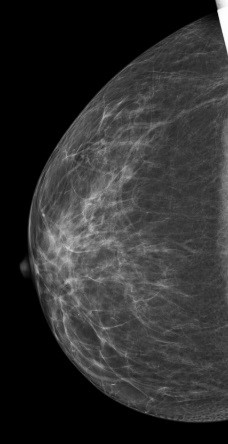

病史:患者,女53岁,体检超声检查提示右乳结节。

2D图像:

常规2D 图像上象限似见小结节,边缘有小毛刺,还可见粗大血管影穿过,CC位上又没发现异常影像,DBT检查后在合成2D图像上表现同常规2D,但在DBT图像的上象限可以清楚见到一小结节,呈分叶状,边界较清楚。

结合DBT考虑病灶为BI-RADS 4A病变。

右乳纤维瘤。